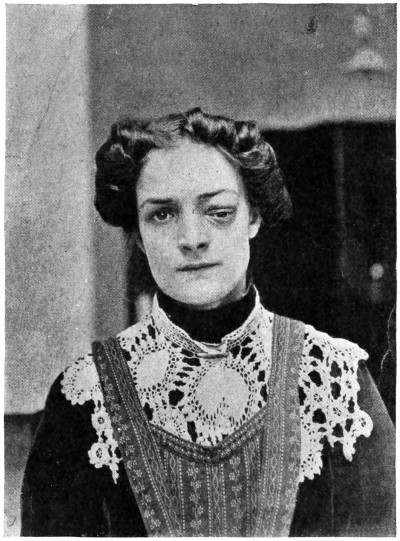

The extent to which the scalp should be shaved and the time at which this procedure should be carried out vary according to the circumstances of the case. Much depends on the sex and age of the patient and the nature of the proposed operation. Insomuch, however, as it is always inadvisable to prolong the period of anæsthesia, it follows that the shaving should be carried out previous to the operation. With regard to extent, each case must be judged on its own merits. For instance, considerable concession must be made in the case of a young woman on whom the surgeon proposes to carry out a subtemporal decompression operation, and in the case of a neurotic or elderly patient who is the subject of trigeminal neuralgia. There can, however, be no question that the limitation of operative field advocated by some surgeons is fraught with considerable risk from the point of view of wound infection.

If the question be discussed with the patient the surgeon will find the ground cut away from beneath his feet, and that he has to make considerable and inadvisable concessions. Taking everything into consideration, although it is seldom necessary to shave the whole head, I am accustomed to order such preparation as will allow of a very wide margin. To shave the whole head is not only unnecessary but is also exceedingly distasteful to the patient. The front, back, or side of the head should be prepared only—on the morning of the operation, so as to allow of a comfortable night’s rest. After shaving, the scalp is thoroughly cleansed with soap and water, and the head[11] surrounded by a sterilized towel. The final skin sterilization is carried out when the patient is under the anæsthetic.